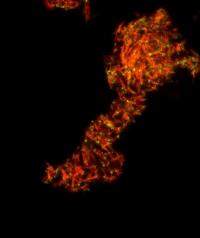

Anteriormente, los científicos en Alemania descubrieron que la transmisión del VIH está relacionada con la presencia de un amiloide fibrilar en el semen. Este fibrilar – una pequeña estructura, con carga positiva derivada de una proteína más grande – promueve la infección por VIH, ayudando a los virus encuentran y se unen a su objetivo: T CD4 células blancas de la sangre. En la edición de mañana de Cell Host & Microbe, los investigadores en el laboratorio de Warner C. Greene, MD, PhD, director de investigación de virología y la inmunología en Gladstone, describe un segundo tipo de fibrillas, que también tiene esta capacidad.

La transmisión sexual es para la inmensa mayoría de las infecciones por el VIH, y el semen es el modo de clave del virus de transporte. Estudios anteriores realizados por los Dres. Roan y Greene revela el mecanismo por el cual una carga positiva fibrilar en el semen – llamada SEVI – atrae el VIH como un imán, la unión a la carga negativa del VIH y ayudar a infectar a las células T CD4. En este caso, se dedicaron a investigar si los otros componentes del semen también jugó un papel.

En experimentos de laboratorio sobre muestras de semen humano, se identificó un segundo grupo de fibrillas -derivados de las grandes proteínas llamadas semenogelins – que mejoran la infección por el VIH así como SEVIhace. La eliminación de estos y otros componentes de carga positiva del semen disminuye la capacidad del VIHpara infectar las células T CD4 de sangre blancas. Lo que confirma el papel de estas fibrillas en la promoción dela infección por

«Nuestros experimentos sugieren que las fibrillas de derivados de semenogelins – el principal componente delsemen – son esenciales para la mejora de la infección por VIH en el semen», dijo Roan. «Pero estamos intrigados por su función natural, biológica y el hecho de que estas fibrillas se encuentran en los órganos reproductivos masculinos podría apuntar a un papel evolutivo en el fomento de la fertilización -.. Algo que estamos estudiando»